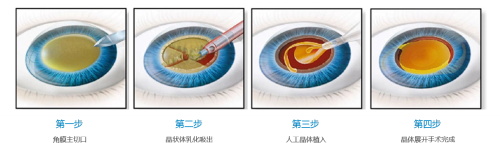

白内障手术是一种非常常见且安心的眼科手术,通常采用超声乳化技术将模糊的晶状体取出,然后植入人工晶状体以改善眼部视力。